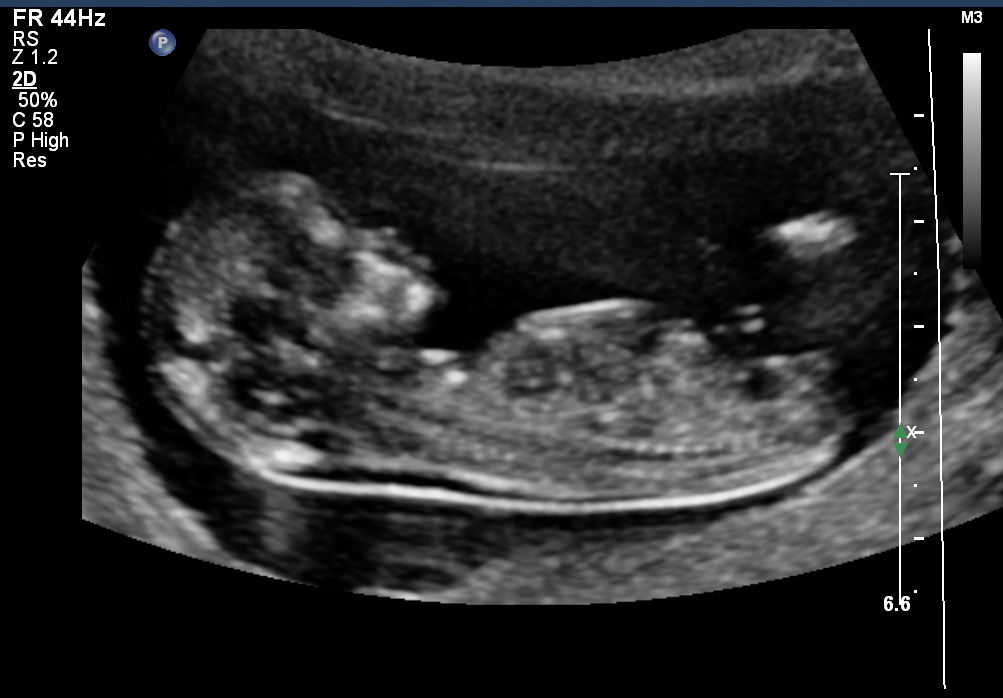

Attachment 5246Attachment 5247

HI i had my scan done at 12 weeks and 1 day(very accurate as i had previous scans) but this bub must of had a growth spurt as it measured 13 weeks on the day. Any ideas of the gender? Would it be more accurate as bub measured 13 weeks?? thanks!!